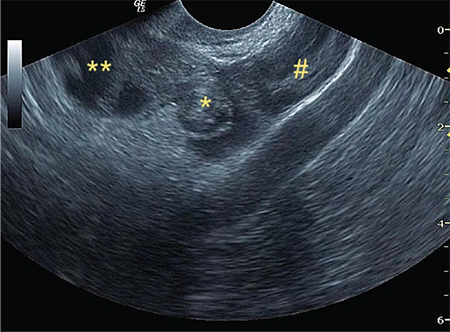

İzole tubal torsiyon: Beş olgunun ultrasonografi ile başarılı preoperatif tanısı ve laparoskopi ile yönetimi

İzole tubal torsiyon, ultrasonografi, , burgaç bulgusu, olgu serisi